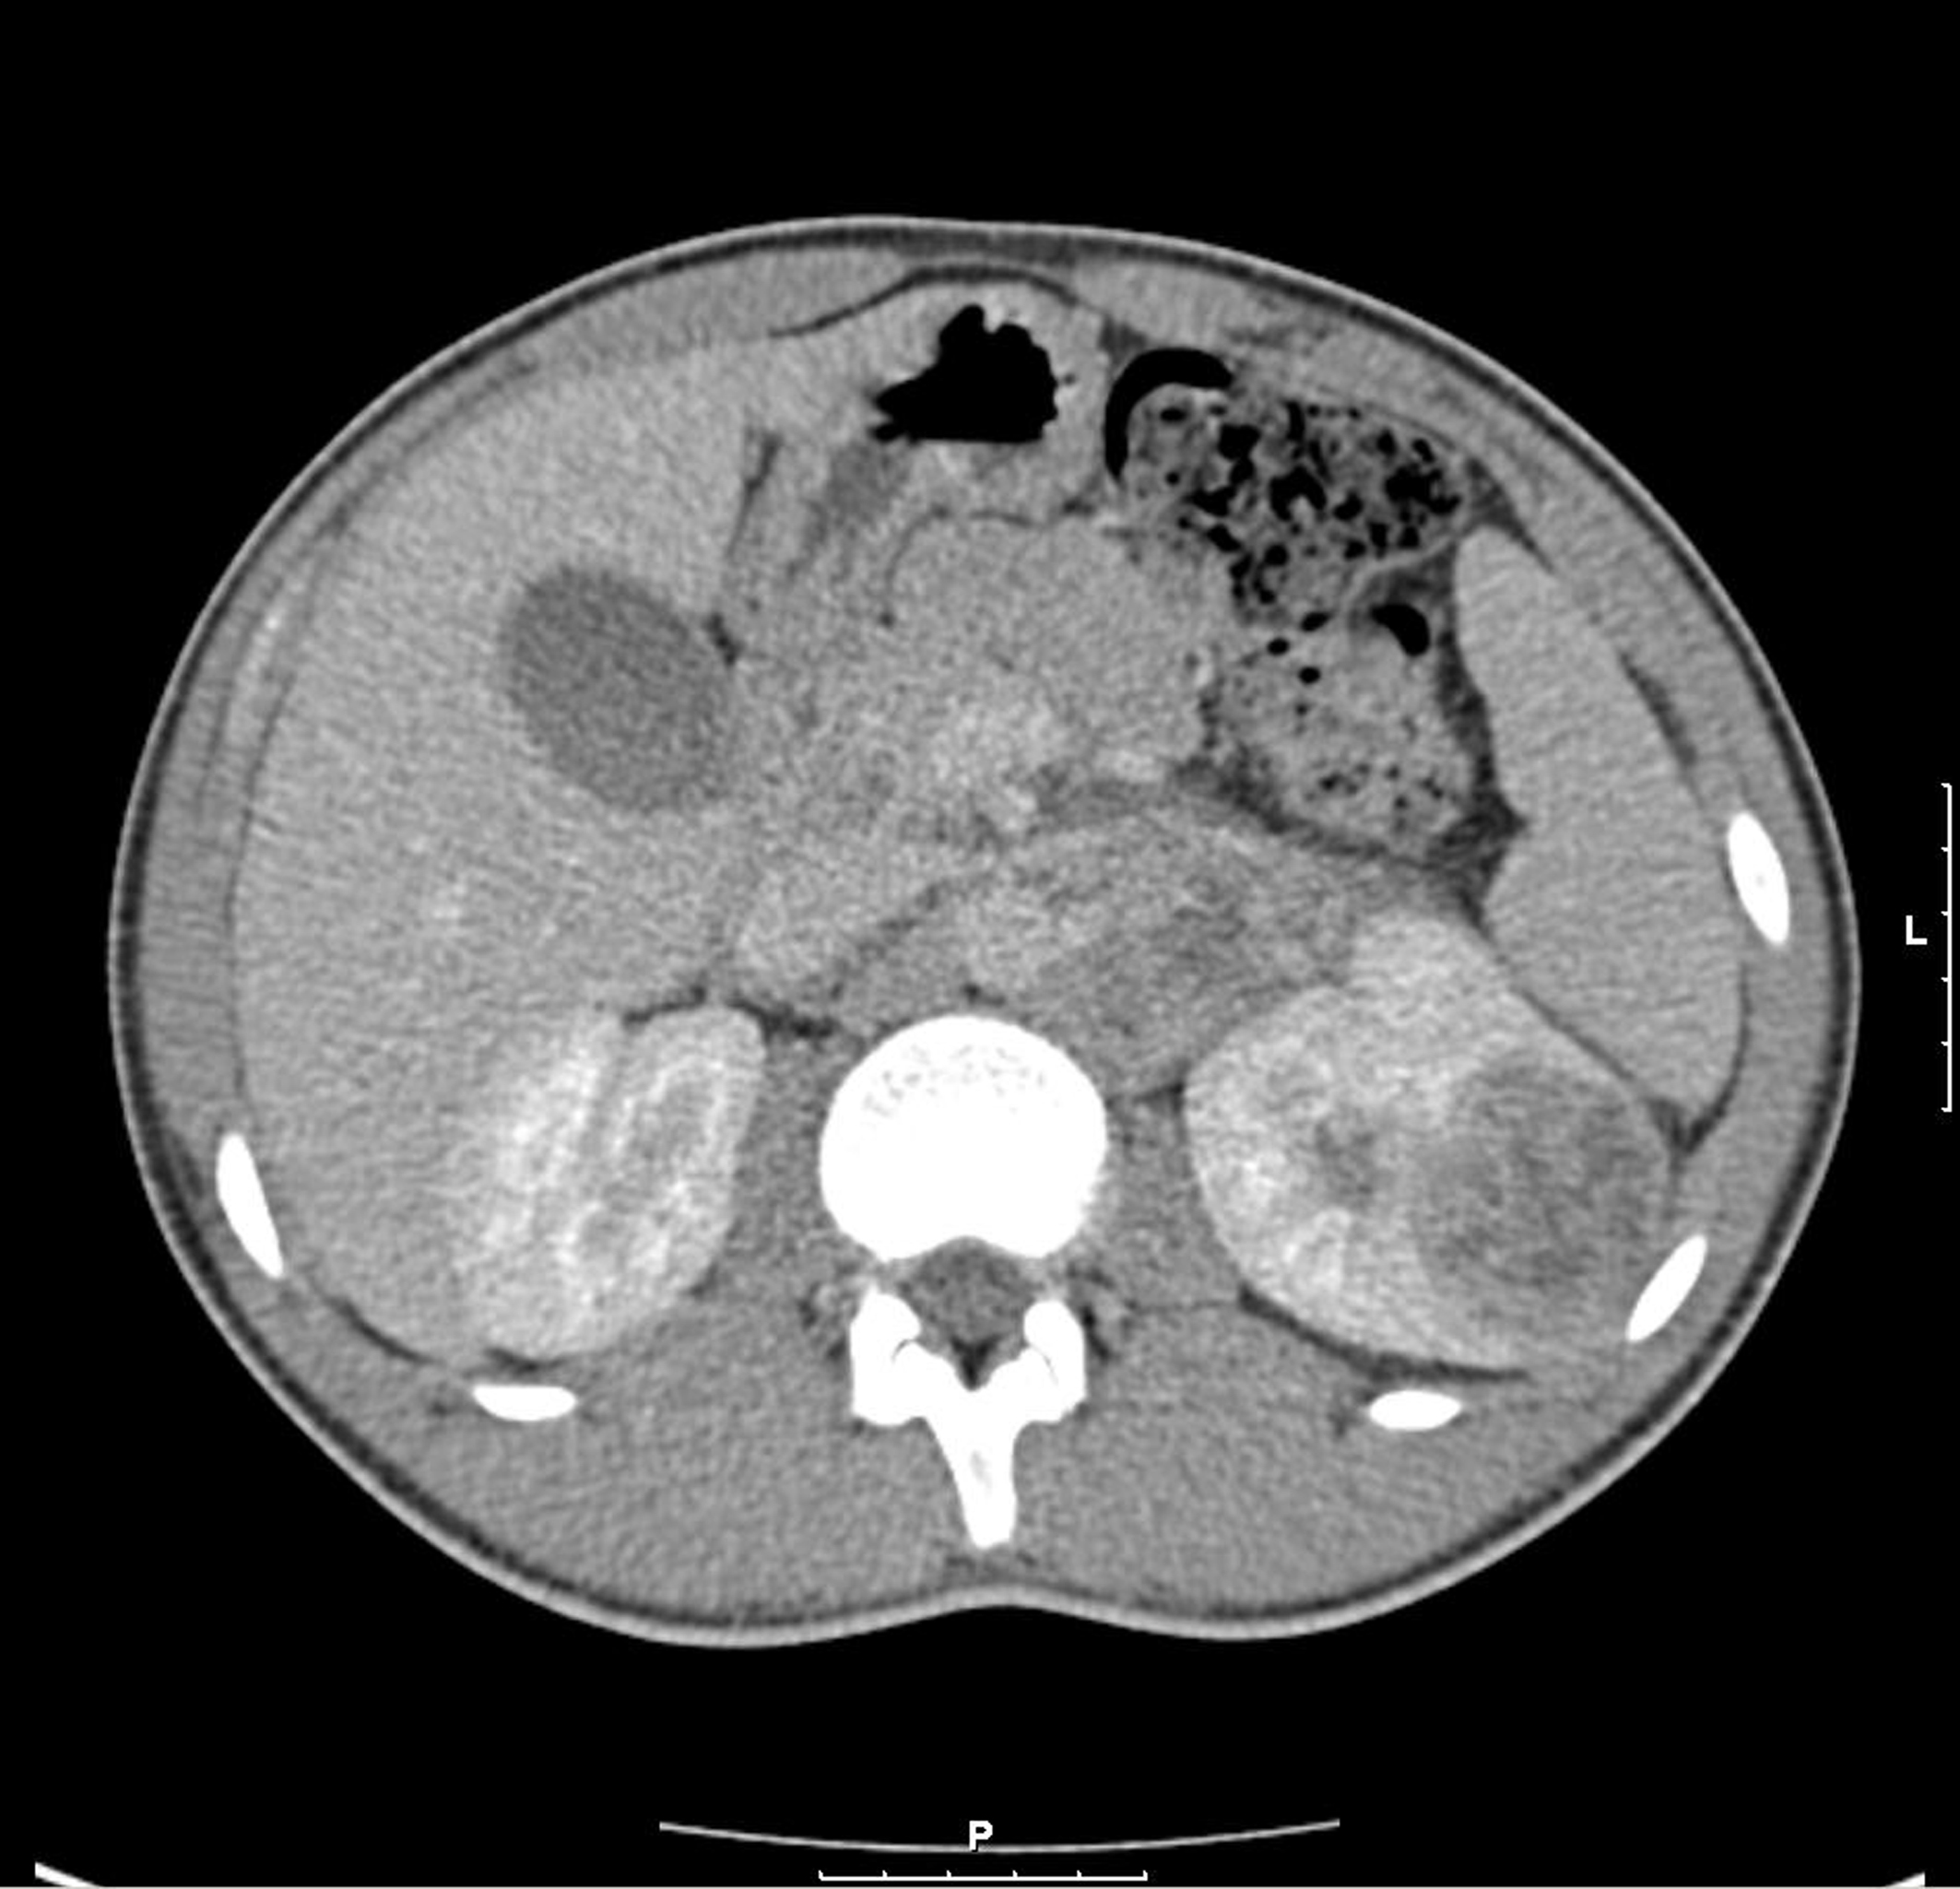

A 3-phase CT abdomen showed the presence of an enhancing mass lesion expanding the superolateral aspect of the left kidney with an extensive abnormal para-aortic lymph nodes mass encasing the renal vessels (Fig. 1). A biopsy of the left kidney mass showed renal parenchyma widely infiltrated by a poorly differentiated adenocarcinoma showing both solid sheets of cells, trabecular arrangements and a micro glandular architecture. The cells showed marked cytological pleomorphism and frequent mitoses with focal necrosis. Lymphovascular invasion was also seen. Interestingly, a red blood cell (RBC) visible in one of the slide looked sickled and raised the possibility of sickle cell disease (Fig. 2). Subsequently, a sickle cell screen was instructive of carrier status with electrophoresis showing HbA 51.0% and HbS 37.5%. On further immunohistology, the end immunoprofile (cytokeratin positive, vimentin positive and CK5, 6 negative) was in keeping with a diagnosis of medullary carcinoma of kidney.

![]() Click for large image | Figure 1. CT shows left renal enhancing lesion with para-aortic lymph node mass. |